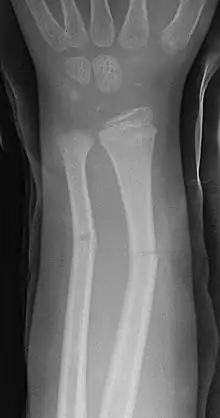

En medicina, se denomina fractura en tallo verde a un tipo de fractura ósea propia de los niños. Afecta a la región central (diáfisis) de los huesos largos, sobre todo en el antebrazo. La denominación en tallo verde procede de la analogía entre este tipo de fractura y la que se produce al intentar romper el tallo verde de una planta.

Se caracteriza por ser una fractura incompleta, con ruptura del periostio y la cortical en el lado de la convexidad del hueso, mientras que en la zona cóncava el periostio no llega a romperse, como consecuencia el hueso no está totalmente roto (fractura incompleta), pero los fragmentos se desplazan y presentan una angulación de amplitud variable que es preciso corregir. [1][2]

Las fracturas en tallo verde afectan por lo general a la porción central o diáfisis de los huesos largos de los niños, sobre todo a la región del antebrazo, muñeca y clavícula. Raramente se produce en otros huesos como la tibia y el fémur. Cuando afecta al antebrazo puede existir fractura del cúbito, el radio o ambos huesos simultáneamente.